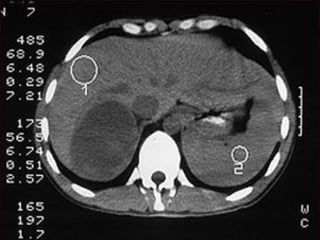

MIELOLIPOMA ADRENAL (D)

MIELOLIPOMA ADRENAL (TAC)